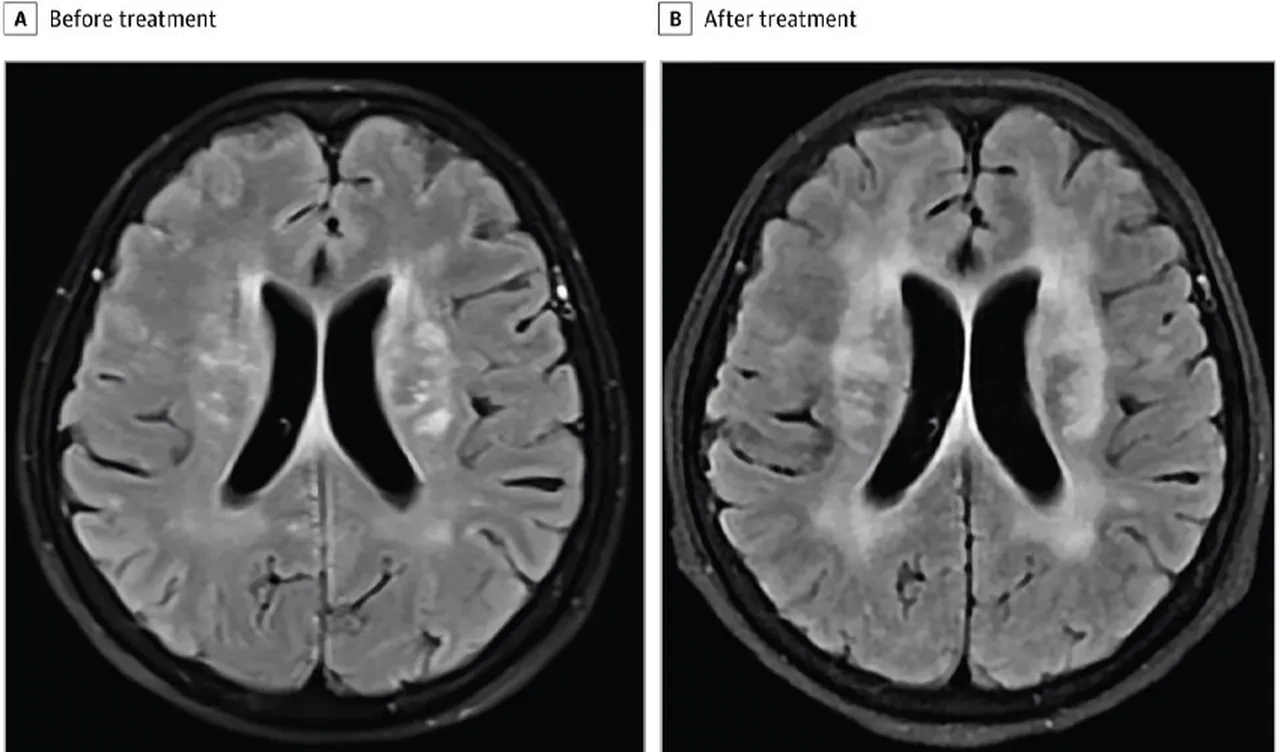

Doktorlar ilk etapta menenjit şüphesiyle harekete geçti. Yapılan tetkitler sonucunda beyninde çok sayıda lezyon tespit edildi ve bu da enfeksiyon ihtimalini güçlendirdi. Ancak iki hafta süren antibiyotik tedavisine rağmen hastanın sağlık tablosu giderek kötüleşti.

Hastaya acilen antiparaziter ilaç verildi. İki hafta içinde konuşma yetisini yeniden geri kazanan hastanın sağlığı da hızla iyiye döndü. Dört ay sonra yapılan kontrollerde beyindeki lezyonların büyük ölçüde küçüldüğü ve hastanın neredeyse tamamen iyileştiği görüldü.